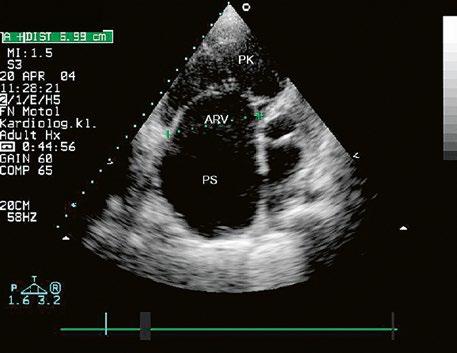

Obr. 45.14 TTE, čtyřdutinová apikální projekce. Kompletní atrioventrikulární septální defekt je označen křížky, představuje komunikaci mezi oběma síněmi i komorami se společnou atrioventrikulární chlopní (AVch)

LK – levá komora, LS – levá síň, PK – pravá komora, PS – pravá síň